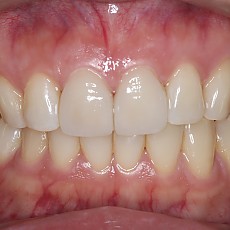

시술전후사진 6 페이지

Total 189건 6 페이지